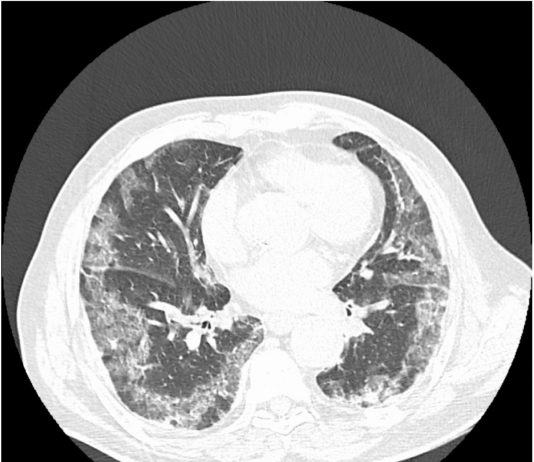

82-years-old female patient, admitted to the ED with dyspnea and fever for 7 days. Medical history: HTA and kidney cancer. Blood test: C-PR 106,93 (< 5); ESR 45 (<15);...